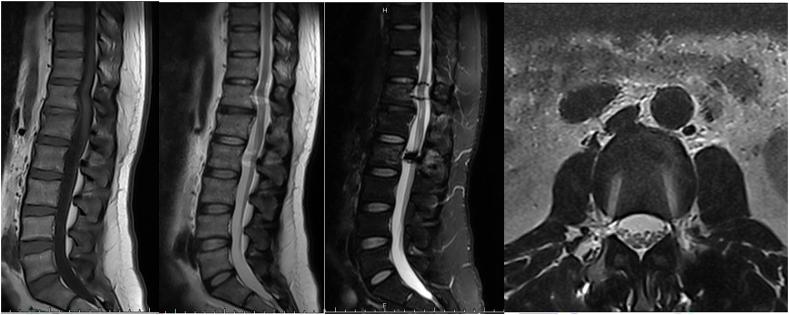

CASE PRESENTATION

A 38-year-old man with left leg weakness and severe back pain after fell down while cycling. Physical examination suggested left hip abduction was 2/5 strength, left dorsiflexion of hallux dorsal extension was 0/5 strength and the left ankle dorsiflexion was 2/5 strength. Magnetic resonance images (MRI) of lumbar spine showed a two-leveled hematoma extending from T12 to L1. After 1 year of surgery, the patient's symptoms had largely disappeared and he was able to perform daily activities independently.

一名38岁男性,在骑自行车摔倒后出现左腿无力和严重背痛。体格检查显示左髋外展肌力为2/5级,左足背屈背伸肌力为0/5级,左脚背屈肌力为2/5级。腰椎磁共振成像(MRI)显示一个从T12延伸至L1的两级血肿。术后1年,患者症状基本消失,能够独立进行日常活动。